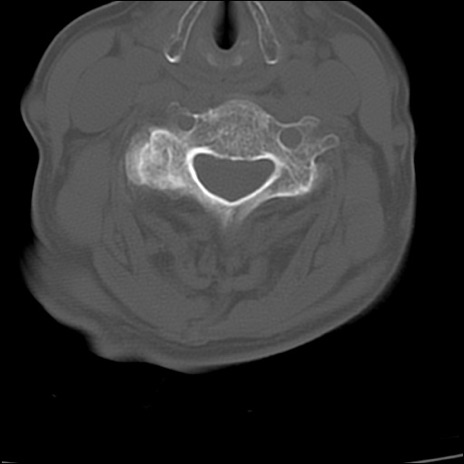

症例48 頚椎CT(横断像)

頚椎CT